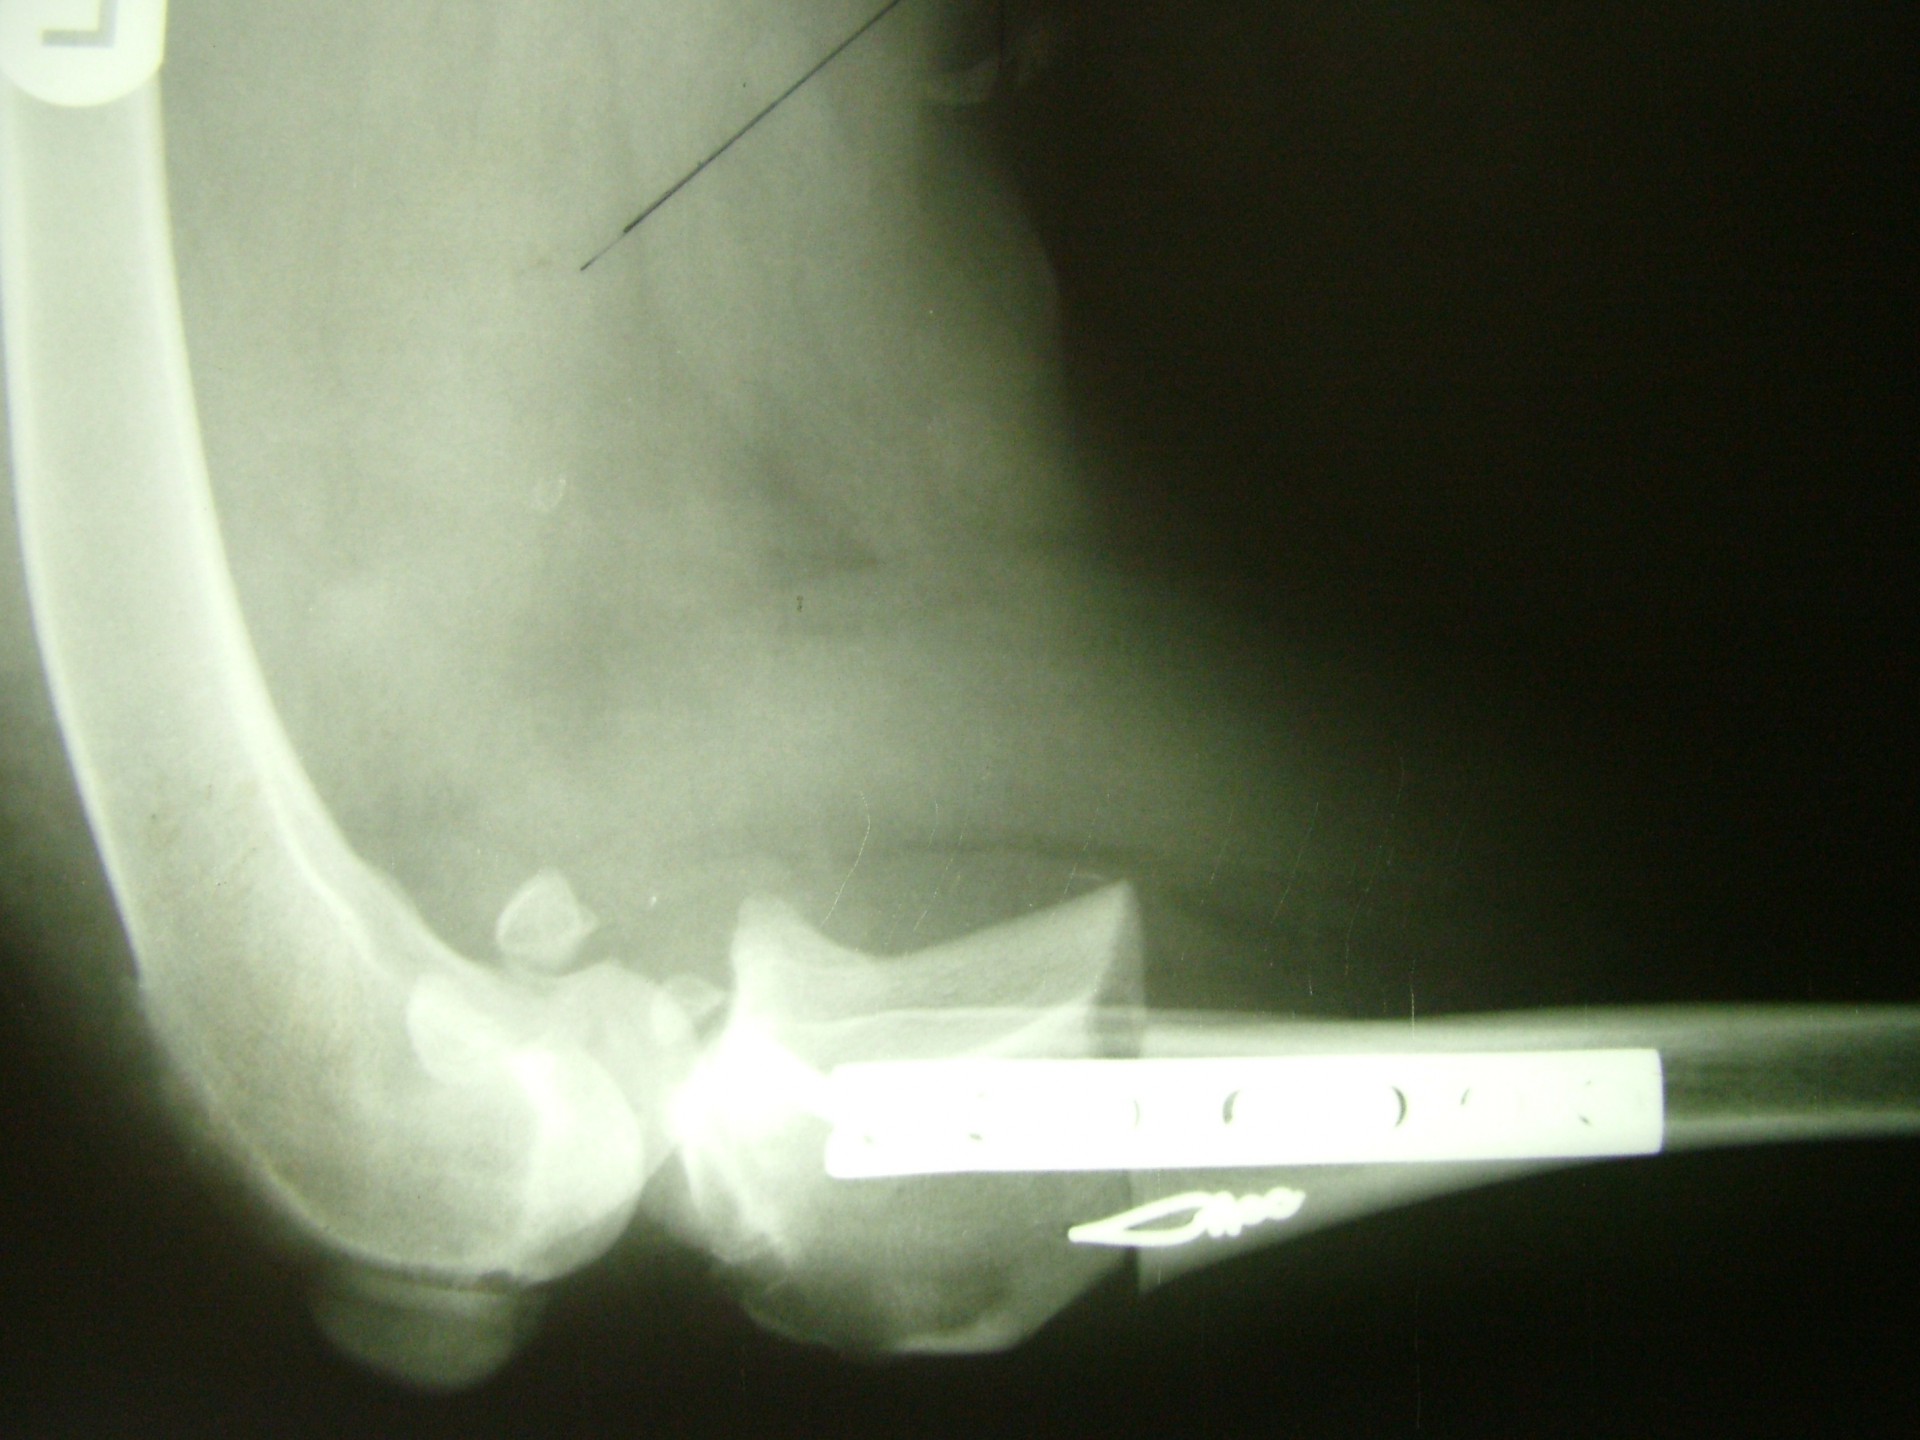

Az utóbbi 25 év egyik legnagyobb előrelépését jelentette a kereszteződőszalag szakadás műtéti megoldásában az amerikai származású Barclay Slocum által kifejlesztett műtéttechnika, mely alapja a szakadásra hajlamosító tényezők és a szalagra ható fizikai erők vizsgálata. Barclay Slocum olyan műtéti technikát dolgozott ki, mellyel a térdízületet az elülső kereszteződőszalagra ható erőkhöz igazítja. Vizsgálatai alapján a sípcsont ízületi felszínének meredeksége (tibia plató szög, tibial plateau angle, TPA) és az elülső kersztezőszalag szakadása között egyértelmű összefüggés mutatható ki. A műtét alapja, hogy a sípcsont ízületi felszínét a sípcsontból kivágott ék, majd azt követő lemezes osteosynthesis segítségével a sípcsont hossztengelyére megközelítőleg merőlegesre állítja be, csökkentve ezáltal a szalagra ható erőket (cranial wedge tibial osteotomy, CWTO).Ezt a technikát továbbfejlesztette: a sípcsonti ízületi felszín szögellésének korrekcióját egy speciális félkör alakú fűrész segítségével, az ízületi felszínt is magába foglaló sípcsonti részlet kivágásával, elforgatásával és rögzítésével oldatta meg (tibial plateau leveling osteotomy, TPLO).

Az utóbbi évek újítása a Slobodan Tepic által kidolgozott technika, mely a térdízületet alkotó szalagrendszert úgy alakítja át, hogy a térdízületre ható erők változnak meg és alakulnak a térdízülethez (Tibial Tuberosity Advancement, TTA).Mivel az eljárás még egészen új hosszú távú eredményessége még nem teljes körűen ismert.